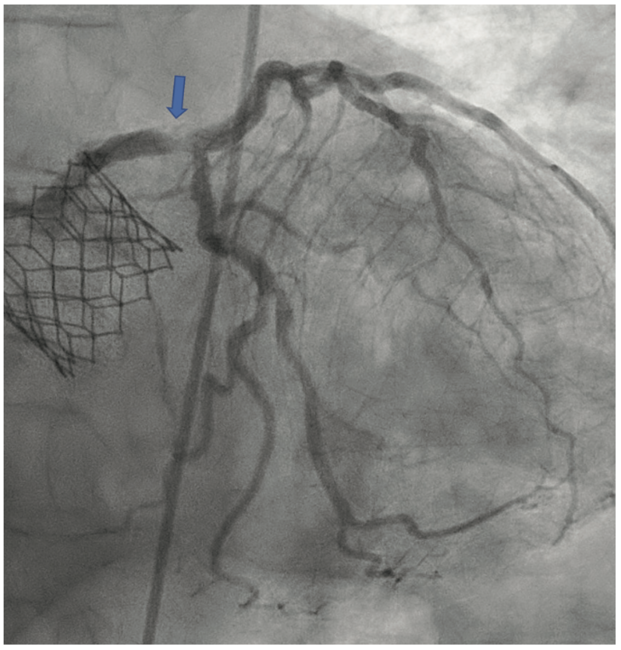

The LM was engaged with a 7 French (F) XB 3.5 guide catheter (Cordis Corporation). A workhorse coronary wire was advanced to the distal left anterior descending (LAD) coronary artery and another workhorse wire was advanced to the distal obtuse marginal. Serial inflations with 3.5 mm x 20 mm NC balloon were performed at 20 atmospheres (atm) in the distal LM. A kissing balloon inflation (KBI) was done using two 3.5 mm x 12 mm NC balloons at 12 atm. The ostium of the left circumflex (LCX) and distal LM was further prepared using a 4 mm x 10 mm Wolverine cutting balloon (Boston Scientific) at 12 atm. The distal LM lesion did not yield, despite multiple balloon inflations. Hence, a 4 mm x 12 mm IVL balloon (Shockwave Medical) was used at 4 atm for 40 pulses. These inflations had to be supported with intravenous norepinephrine boluses. Later, a 4 mm x 12 mm NC balloon was used and the result showed adequate expansion across the LCX ostium. A double-kissing culotte was completed and the proximal LAD was stented with a 3.5 mm x 24 mm Synergy Megatron (Boston Scientific) at 12 atm. Proximal optimization technique (POT) was performed using a 5 mm x 12 mm NC balloon at 20 atm. The LCX was re-crossed using another workhorse wire and the jailed LCX wire was removed. The side struts were opened using a 2 mm x 12 mm semi-compliant balloon, followed by KBI with two 4 mm x 12 mm NC balloons at 12 atm. Re-POT was done using 5.5 mm x 12 mm NC balloon at 22 atm with an excellent result (Figure 4). The final IVUS demonstrated a MSA of 11 mm2 in the distal LM, and 9 mm2 MSA was attained in the ostium of the LAD and LCX (Figure 5). Total contrast used in the procedure was 30 mL, as IVUS was used significantly during the PCI in view of the complex lesion, as well as the patient’s pre-existing renal impairment. He was discharged the next day after post PCI hydration with dual antiplatelet therapy for six months and he had no change in creatinine at the end of one week. At four weeks, the patient is well without any angina and is asymptomatic from a cardiac perspective.